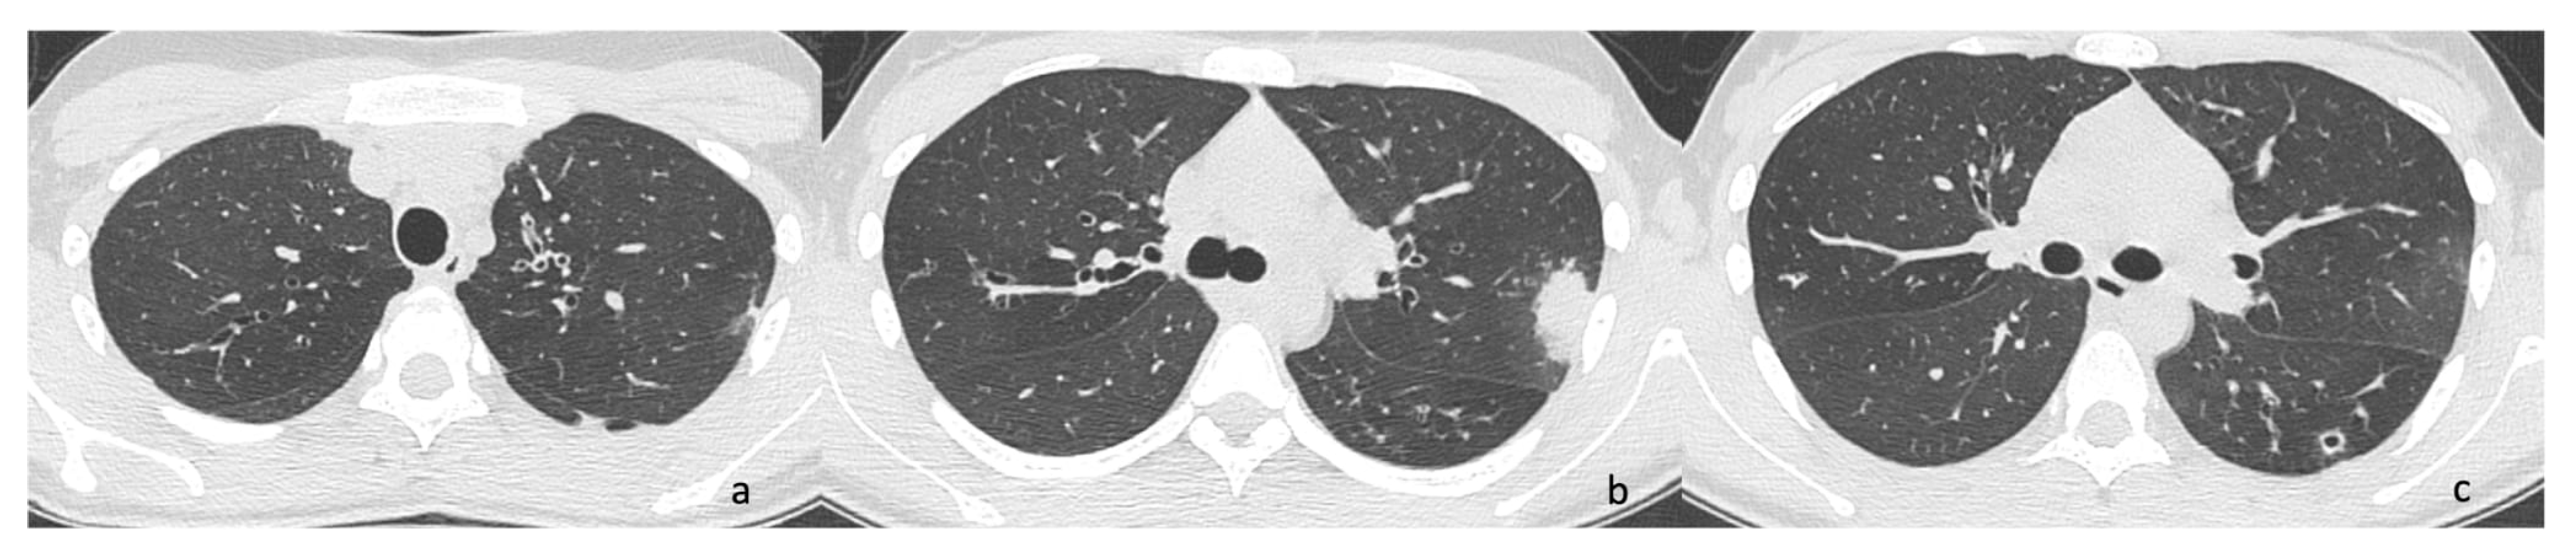

2.1. Case 1

2.2. Case 2

2.3. Case 3

2.4. Case 4

| VE01 | 18 | Haemophilus spp.; PA | Cough, increased secretions | Chest CT: consolidation and mucous plugs, new tree in bud aspect in the lingula, upper and lower lobe, left lower lobe consolidation. | 94 | 107 | 19.59 | NA | Amikacin and Ceftazidime (14 days) ˜ | No |